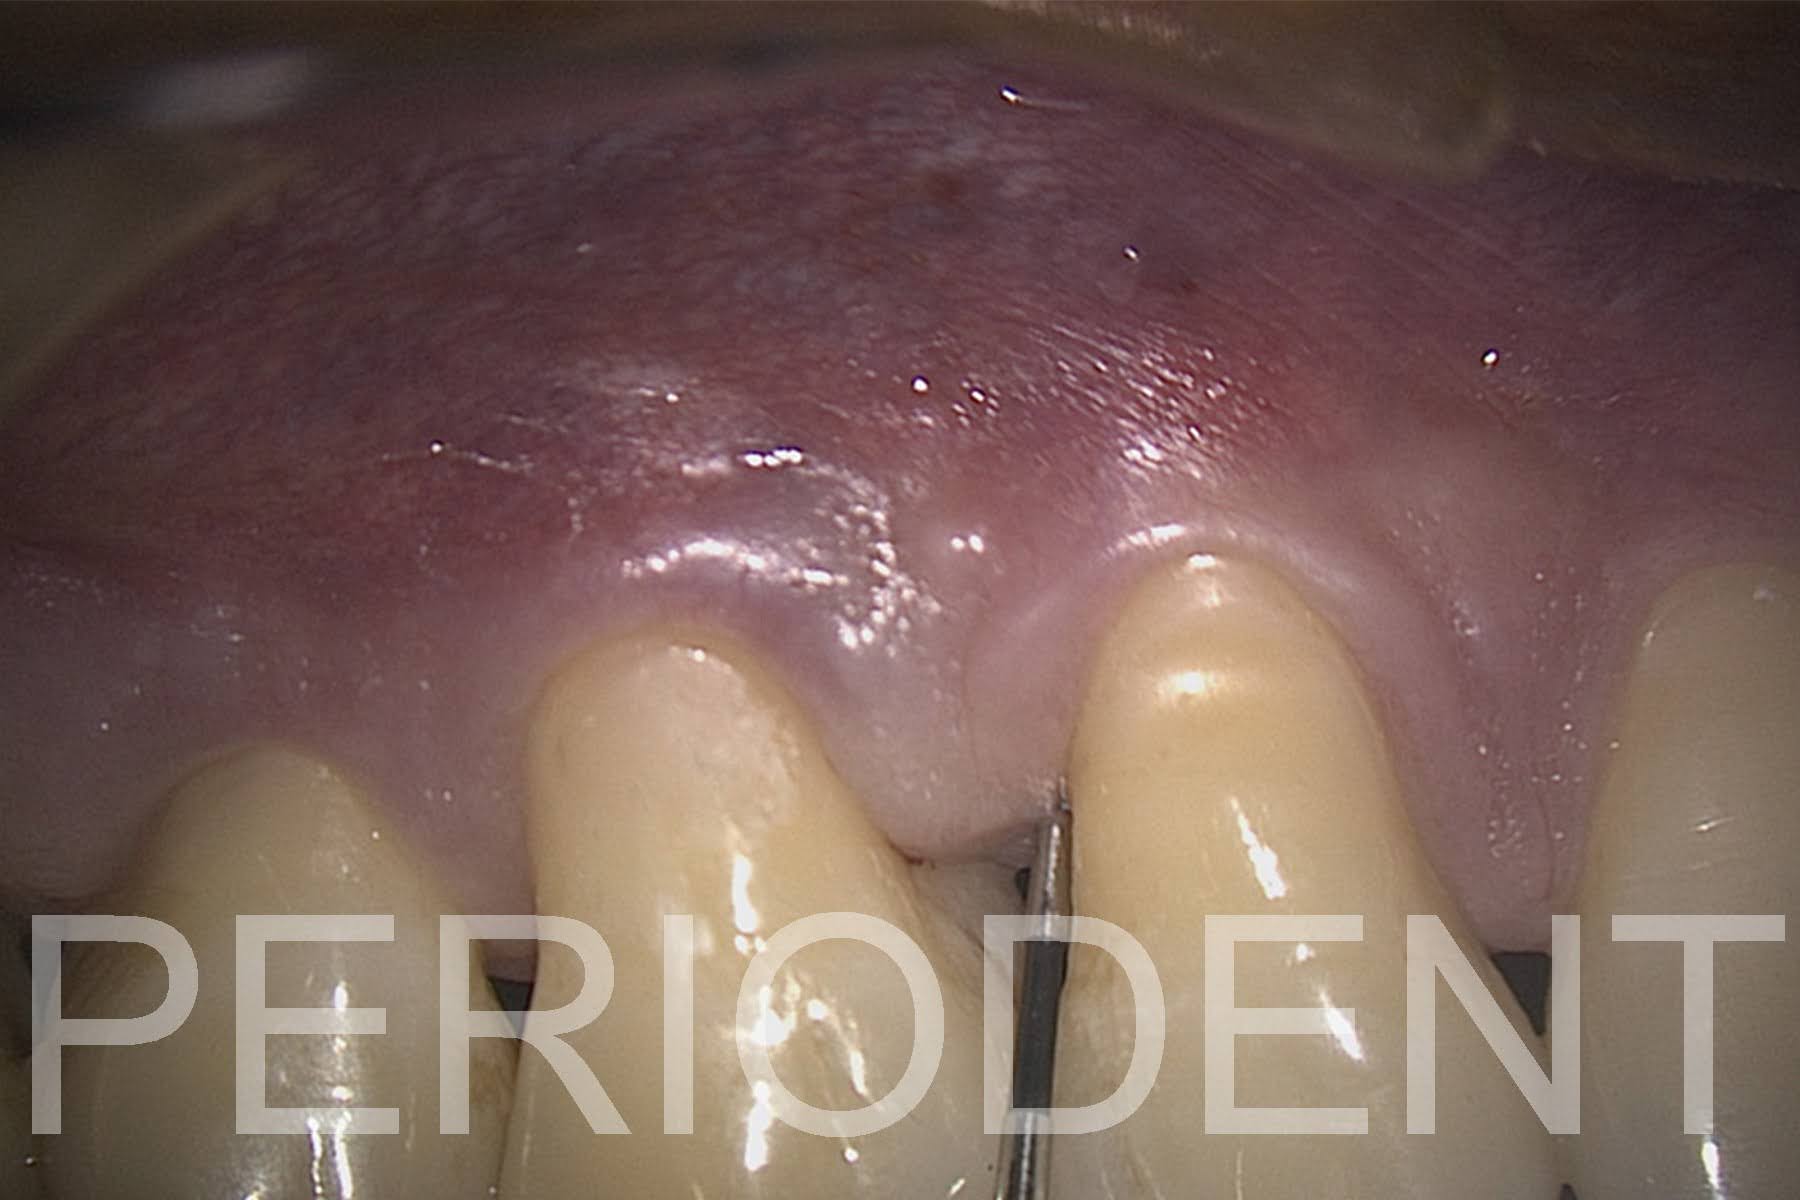

5.    一星期觀察時